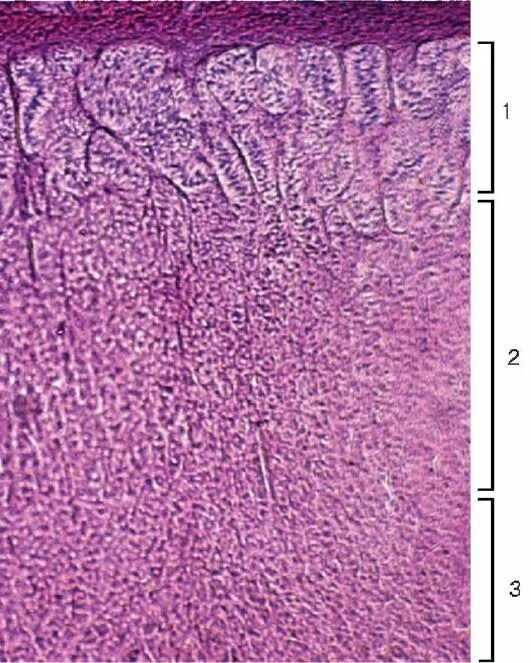

Гистологический срез это